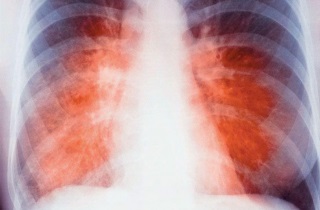

Туберкулез легких

Туберкулез легких — серьезная проблема современности. Заболевание все чаще затрагивает молодое поколение и не ограничивается социально уязвимыми группами. Одной из причин этого является массовый отказ от вакцинации против этого опасного недуга. Также на распространение туберкулеза влияет отсутствие регулярных медицинских осмотров, которые в советское время проводились на всех предприятиях и в образовательных учреждениях.

Наиболее тревожным является то, что на начальных стадиях болезнь может протекать практически без симптомов. Возбудитель туберкулеза (туберкулезная палочка) проникает в организм через кровь или воздушно-капельным путем, образуя небольшие очаги воспаления. Долгое время единственным признаком может быть легкое покашливание, которое со временем усиливается и становится более частым и приступообразным.

На ранних этапах туберкулез легко перепутать с кашлем курильщика. Поэтому у людей с этой вредной привычкой заболевание часто диагностируется поздно, когда появляется постоянный изнуряющий кашель и отхаркивание мокроты с примесью крови. Это может указывать на открытую форму туберкулеза, представляющую опасность как для пациента, так и для окружающих.